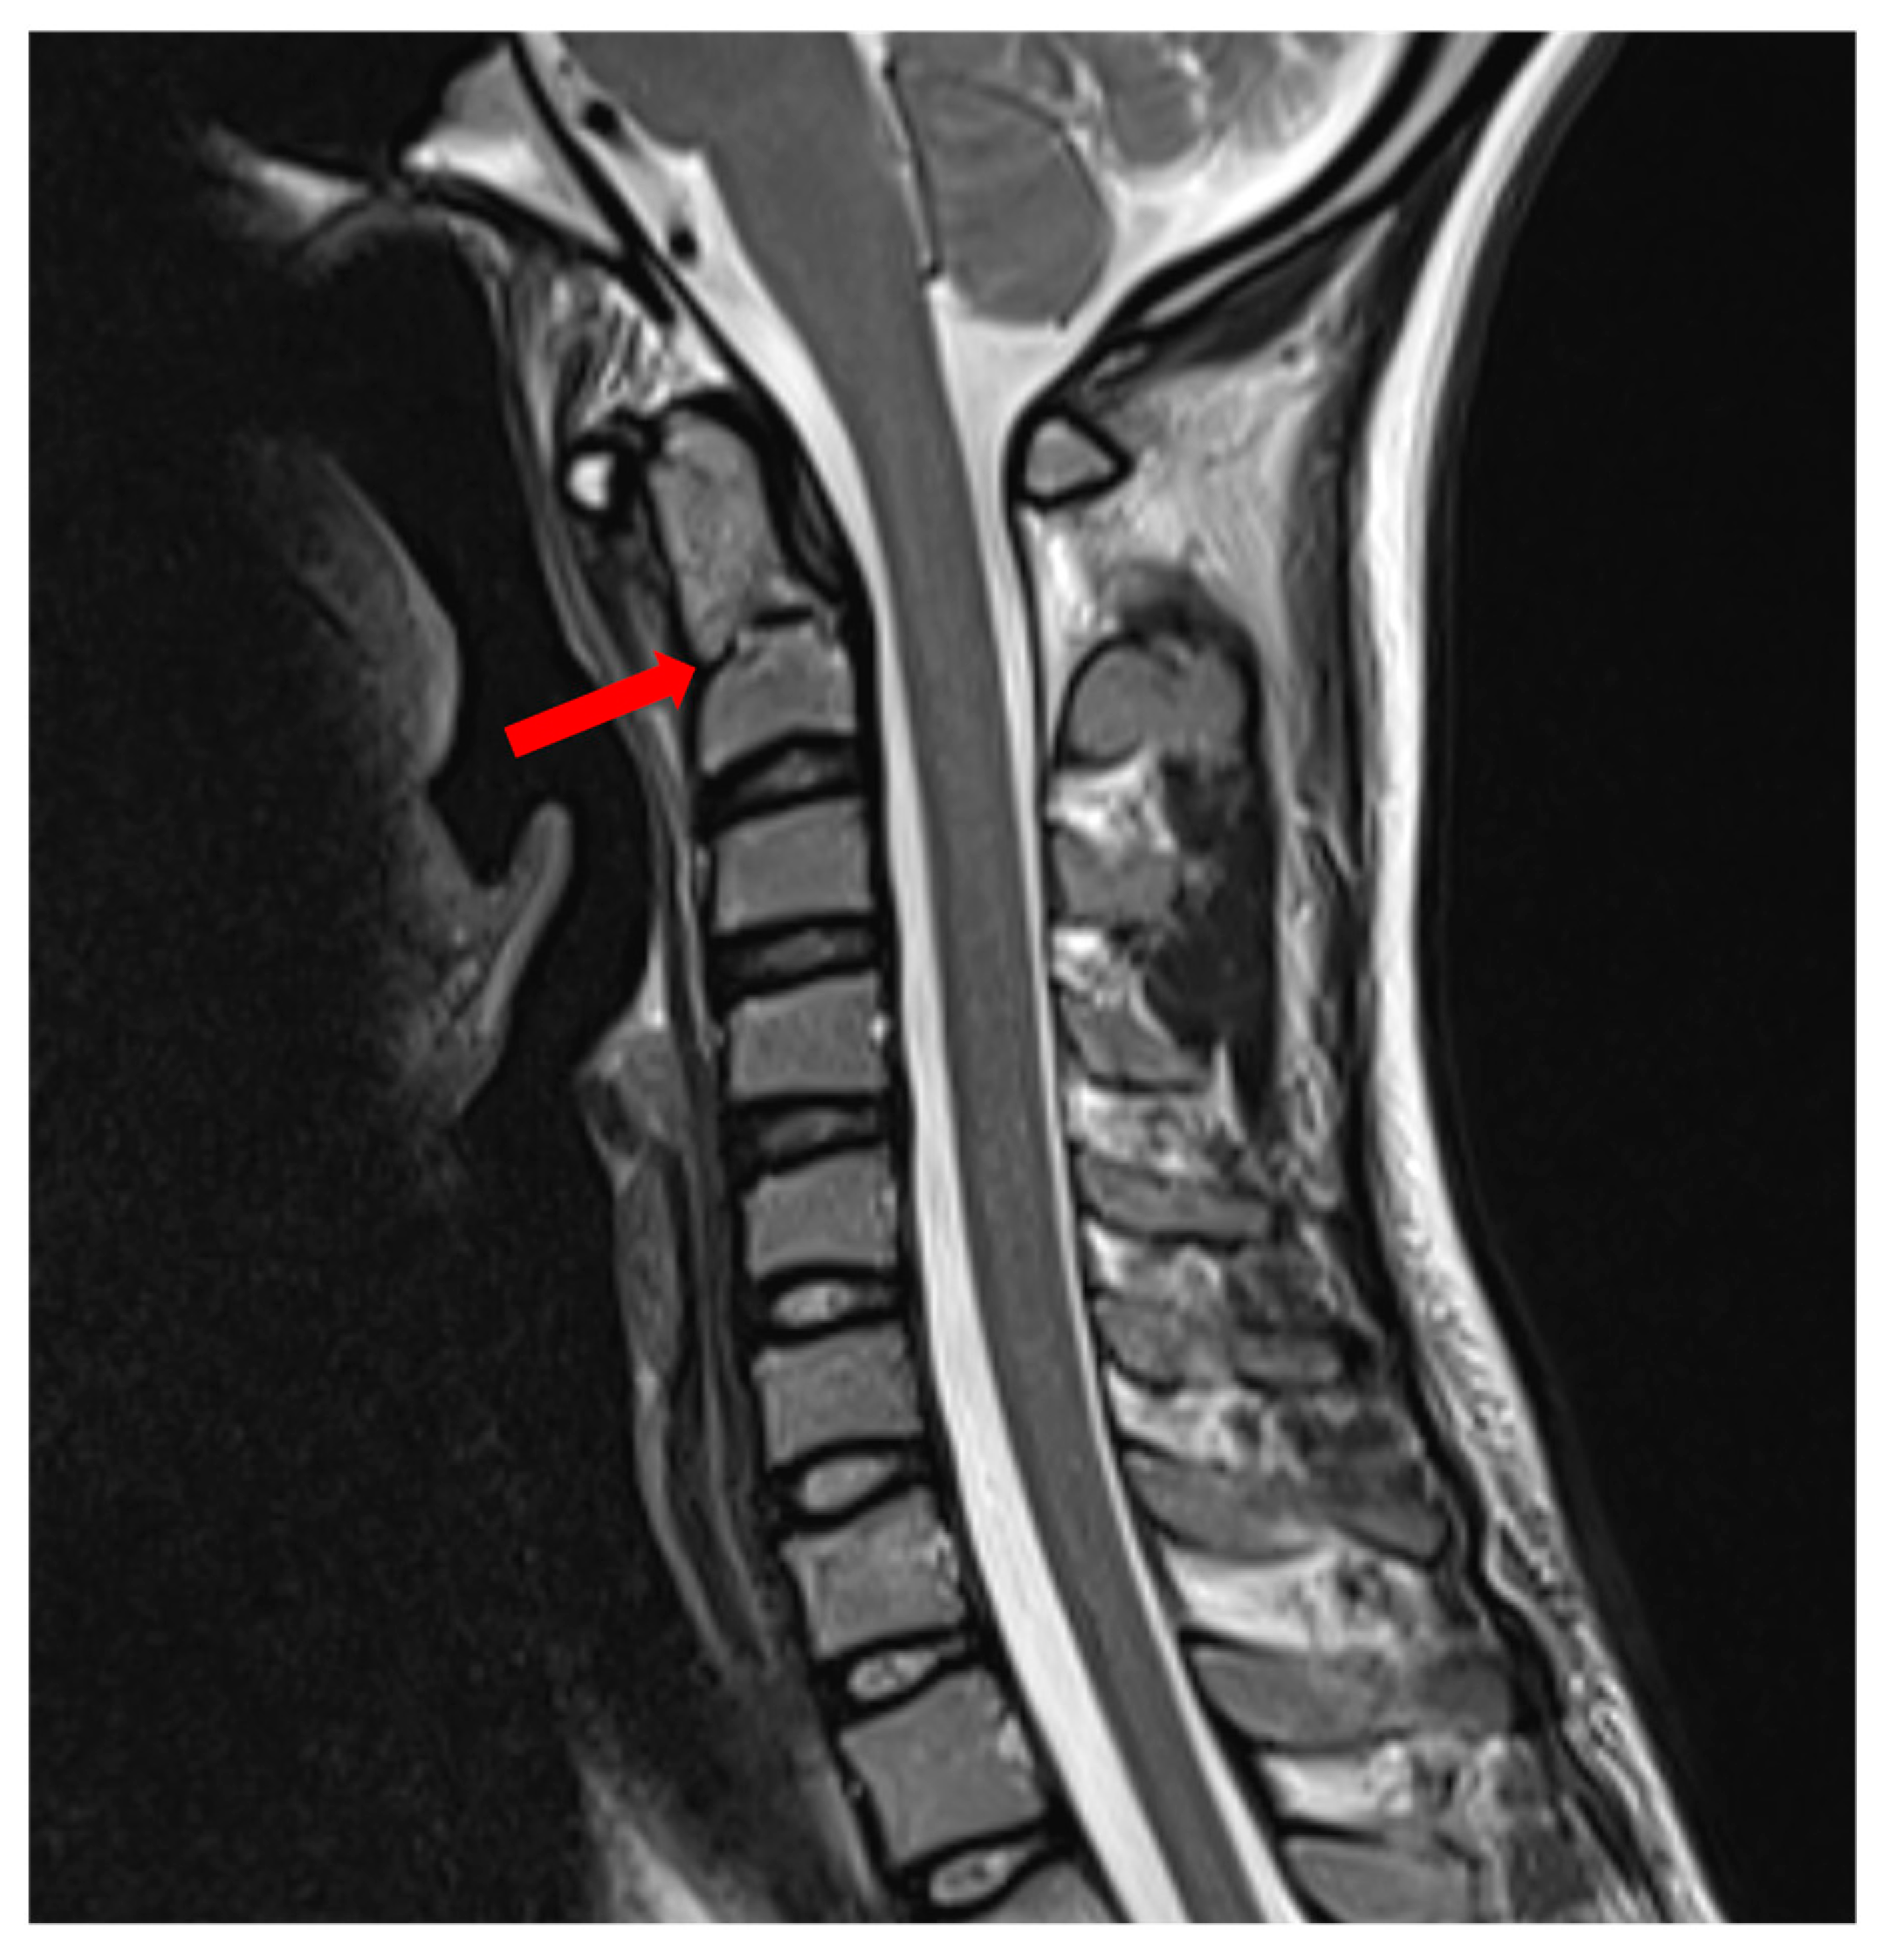

Figure 1. Sagittal neck MRI, revealing the C2 Durel Type II subclass C fracture, Red arrows indi-cate the fracture site. A 19-year-old female athlete endured an unfortunate incident while participating in the European championship for short-track speed skating. During this accident, she sustained a significant facial impact, which led to the onset of distressing symptoms. Upon immediate evaluation at the athletic center medical facility, the patient re-ported severe craniocervical pain, rating it at a distressing 8/10 on the visual analogue scale (VAS). Physical examination revealed that any movement involving neck flexion, extension, or rotation exacerbated her pain significantly, resulting in a VAS score 10/10. In response to the incident, an X-ray examination was promptly conducted, and it revealed no apparent injuries, leading the medical team to grant her clearance to resume the competition. Remarkably, on the day of the accident, the patient showcased remarkable resilience by continuing and successfully completing three additional rounds of rac-ing.Despite her initial resolve, the patient endured ongoing discomfort, rating her pain at 4/10 on the VAS scale. Surprisingly, she actively participated in three more competitions involving at least 20 short-track speed skating rounds during this period. This discomfort persisted for an extended 29-day duration after the incident, leading to an MRI being conducted at a different hospital than ours. The radiologist at the external facility reported an old C2 Durel Type II, Subclass C fracture (Figure 1). Ongoing pain led the radiologist to refer the case to our department. Upon the patient’s arrival at our institution 41 days after the injury, the clinical presentation, recent accident history, and the extent of the fracture, which involved approximately one-third of the odontoid diameter, raised suspicions of a fresh fracture related to the accident. Subsequently, we performed a CT scan and a functional cervical spine CT, both of which confirmed the instability of the C2 Durel Type II, Subclass C fracture. The functional CT examination revealed a 5 mm movement in the fracture line (Figure 2). On the 45th day after the initial injury, the patient underwent a successful surgical procedure, utilizing intraoperative O-arm CBCT and Stealth Station Navigation System (SS8) for C1-C2 dorsal fusion, where we placed bi-lateral screws in the lateral masses of both C1 and C2 and connected them with a rod (Figure 3). This surgical intervention led to the successful repositioning and stabilization of the C1 odontoid (Figure 4). Following the surgical procedure, the patient embarked on a comprehensive rehabilitation program starting six weeks post-surgery. By the 12-week mark post-surgery, she had made a remarkable recovery, regaining full functionality, and was actively participating in speed skating training without experiencing any complaints. Now, 9 months after the incident, she was granted the medical clearance to be called to represent her home country in the following international ice-skating competition due to her amazing speedy recovery. In a broader context, it is noteworthy that over 14 years, from February 2009 to February 2023. Among 347 cases of C2 odontoid fractures, only 5 fractures (1.14%) in our institute were attributed to professional sports activities. These sports-related fractures encompassed cases linked to skiing, short-track speed skating, cross-motorcycling, and go-karting. Notably, 3 of these fractures occurred during winter sports. Different treatment modalities were employed for these cases, with ventral odontoid screw fixation used in two instances, dorsal C1-C2 screw fixation in 1 case, and the HALO fixation device employed in the remaining 2 cases. In general, evaluating an acute cervical spine injury is challenging. Clinicians recommend obtaining three distinct views of the cervical spine. These views encompass the anteroposterior, cross-table lateral, and open-mouth odontoid cervical radiographs [1,2]. However, due to the inherent limitations of conventional plain radiography, the standard approach has evolved to encompass the more widespread utilization of flexion/extension radiographs, CT scans, and MRI examinations, particularly for detecting subtle cervical spine injuries [3]. CT scans have emerged as the modality for effectively visualizing the cervical spine. Consequently, when CT imaging is deemed necessary, there is often no prerequisite for additional plain radiographic imaging [4]. Recent empirical data has suggested that CT imaging should be prioritized to assess the cervical spine rapidly and efficiently, potentially rendering conventional plain radiographic imaging unnecessary [5]. Moreover, in specific clinical scenarios such as neurologic deficits, the need to assess ligamentous injuries, or the imperative to rule out underlying pathologies, MRI may also be considered an invaluable diagnostic tool [6,7]. In light of the absence of clear-cut guidelines regarding the optimal imaging modality for cervical fracture diagnosis, healthcare professionals must thoroughly understand the strengths and limitations of each option. In athletic events, continuous video recording can offer invaluable insights into the injury’s nature, assisting clinicians in making an informed choice regarding the most suitable imaging technique. The selection of an imaging method plays a pivotal role in determining the accuracy and speed of diagnosis, ultimately affecting patient outcomes. While CT and MRI remain the foundations of cervical fracture diagnosis, clinicians must adopt a holistic approach. This involves relying on imaging results and considering the clinical presentation, mechanism of injury, and any associated symptoms [8,9]. The synergy between the patient’s anamnesis, clinical picture, and imaging modalities ensures a comprehensive evaluation, minimizing the risk of misdiagnosis. As the field advances, ongoing research and collaboration between radiologists, neurosurgeons, and orthopedic specialists will be crucial in refining diagnostic protocols ensuring that patients receive timely and appropriate care.

Preprints 87921 g001